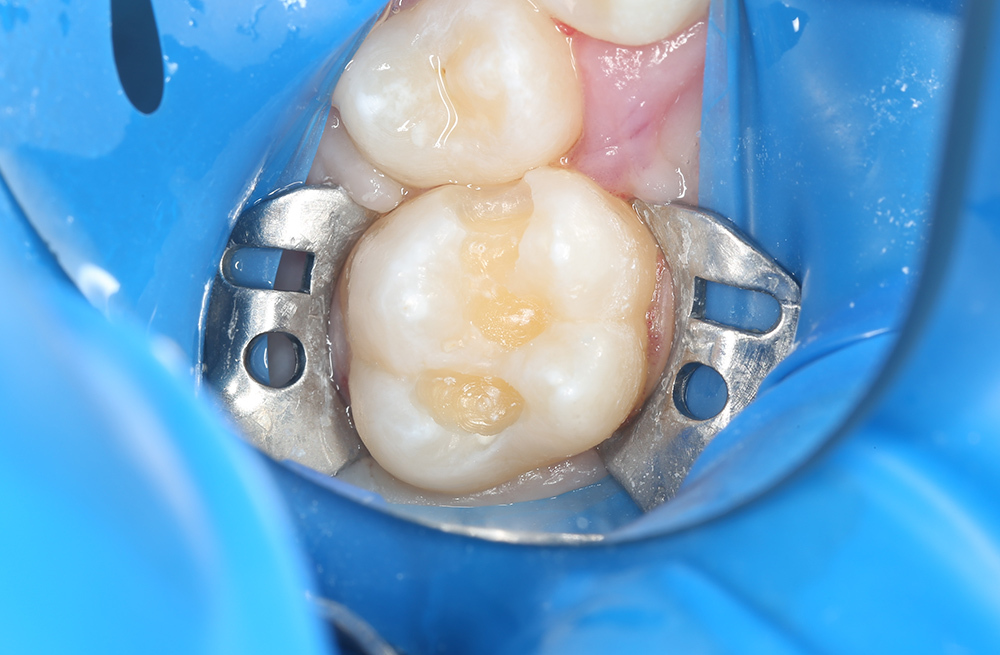

Пломбирование кариозного дефекта коренного зуба с сохранением здоровых тканей